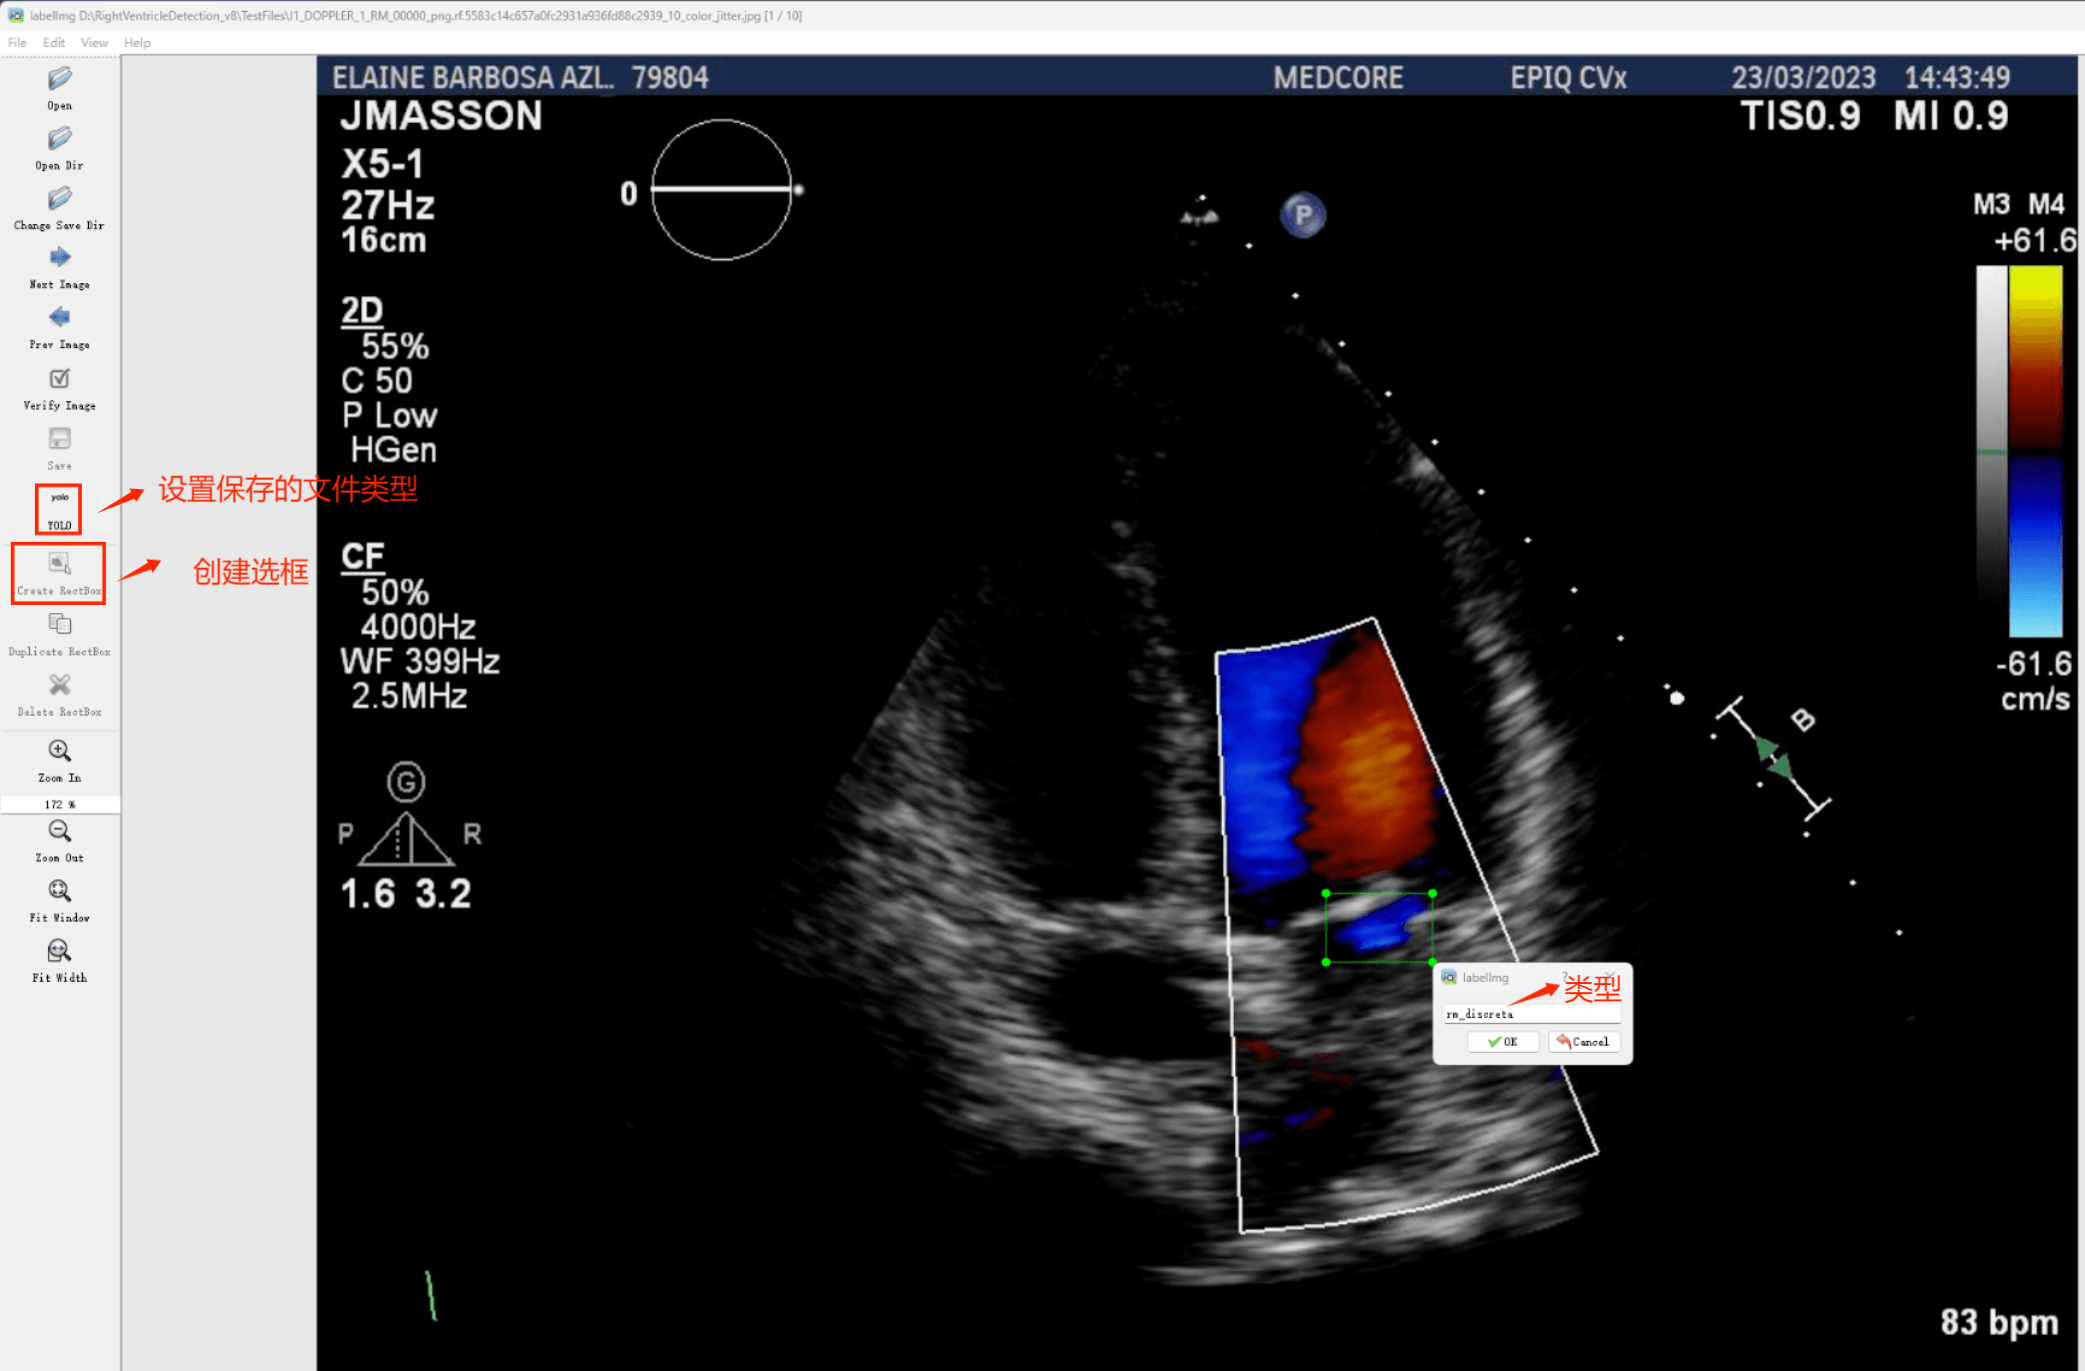

Tipps:为了收集涉及心脏右心室医学影像分析的各种不同类型的图像数据,并利用Labelimg标注工具对每张图片进行精确的注解。采用二分类检测技术将所有样本分为两类:一是'右心室正常';二是'轻微Right Systolic Dysfunction'.

目标检测标注工具

(1)LabelImg:一款开源的图像标注工具软件,默认功能支持分类与目标检测任务处理,并且它是由Python语言开发完成的,并且采用Qt图形界面设计风格,默认界面较为简洁易用(虽然为英文界面)。其标注结果以PASCAL VOC格式保存为XML文件格式数据文件类型,默认也是ImageNet数据集使用的数据格式类型之一。此外该软件还支持COCO数据集格式的数据导入与处理操作。(2)在CMD窗口中执行以下命令完成LabelImg软件包的安装操作:pip install labelimg -i https://pypi.tuna.tsinghua.edu.cn/simple

结束后,在cmd中输入labelimg

初识labelimg

打开后,我们自己设置一下

在View中勾选Auto Save mode

接下来我们打开需要标注的图片文件夹

请指定保存标注文件的目标目录(如同一界面中的Change Save Dir)。随后启动标注流程,在图像窗口中执行以下操作:首先对目标进行边界框绘制并在其标签旁添加对应的分类标签;完成当前图片的标注后切换至下一张图片继续操作。